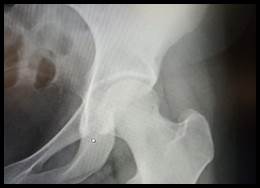

En el balance lesional primario no se constataron lesiones de órganos nobles, en tanto que a nivel osteoarticular se destaca posición viciosa a nivel de miembro inferior izquierdo en rotación externa, abducción y flexión (Figura 1), sin alteraciones a nivel de piel ni de la esfera neurovascular. Valorado en primera instancia en puerta de emergencia del Hospital de Carmelo, las radiografías iniciales (Figura 2) evidencian una luxación anterior de cadera izquierda tipo obturatriz, por lo que es enviada al Centro Hospitalario Pereira Rossell para su resolución. Al momento de arribar con 10 horas de evolución y sin cambios clínicos, se procede a reducción cerrada de la cadera en block quirúrgico bajo anestesia general, traccionando en el eje de la deformidad con cierto grado de rotación interna, logrando reducción exitosa controlada bajo intensificador de imagen y estabilidad clínica en todos sus ejes de movimiento (Figura 3). Durante el postoperatorio inmediato, se constata indemnidad neurovascular del miembro y se realiza Tomografía Computada (TC) de la cadera afecta sin evidenciar trazos de fractura, fragmentos intraarticulares ni desplazamiento epifisario (Figura 4). Con buena evolución en sala, se otorga alta a domicilio con descarga del miembro afecto por 3 semanas y control en policlínica de ortopedia infantil en 1 mes.

Figura 2:  Radiografía al ingreso